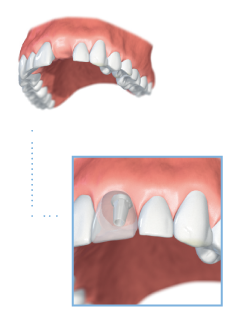

Single tooth replacement

If a single tooth has been lost due to an accident a dental implant can provide a reliable long-term solution in many cases. This treatment does not require any cutting of the adjacent teeth – such as would be the case with a traditional bridge.